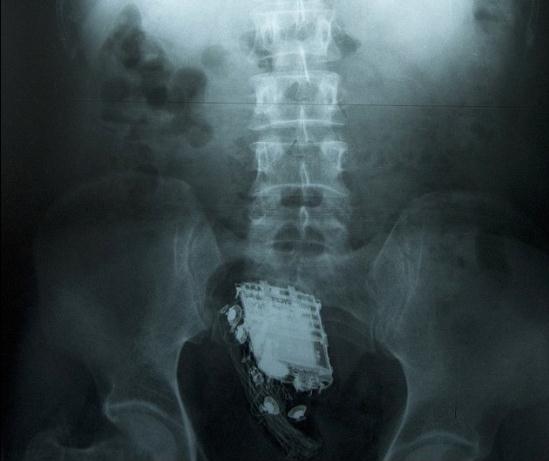

這名58歲的男子因偷盜罪被判處10年監禁,目前正在斯里蘭卡首都科倫坡的韋利卡達監獄服刑。為了能把手機順利取出,獄警后來把他送進了醫院。X射線掃描顯示,手機被深深地塞進了直腸里。